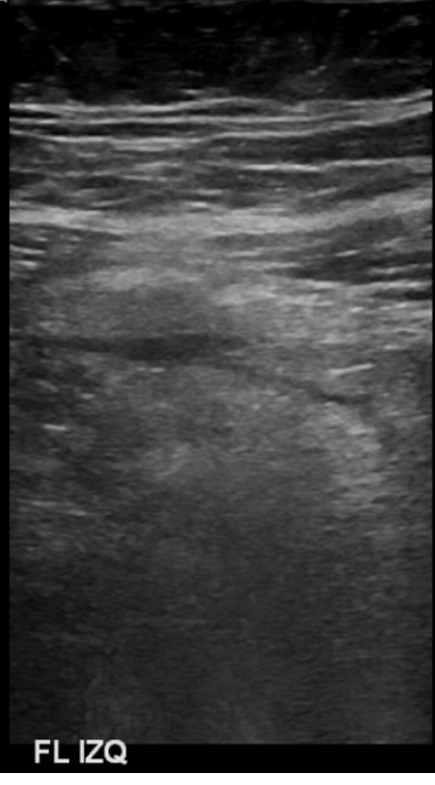

Examen limitado por meteorismo. Páncreas parcialmente visualizado. Hígado aumentado de ecogenicidad con área de respeto periportal sugerente esteatosis difusa moderada. En región dolorosa en FII se observa imagen pseudonodular hipoecogénica, con aumento de ecogenicidad de la grasa adyacente, sin relación intestinal evidente, sugerente apendagitis epiploica.

Hallazgos ecográficos sugerentes de apendicitis epiploica a nivel del flanco izquierdo. Cambios de esteatosis hepática leve. Resto del estudio ecográfico abdominal sin hallazgos significativos.